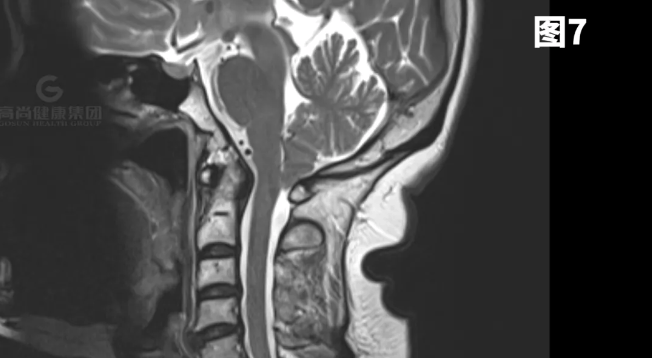

图1-7示小脑扁桃体向下疝出约8mm。

矢状位:扁桃体延伸到枕骨大孔下方,脑干压迫斜坡。

横断位:移位的扁桃体导致周围脑脊液闭塞、髓质前移以及脊髓动脉和椎动脉受压。